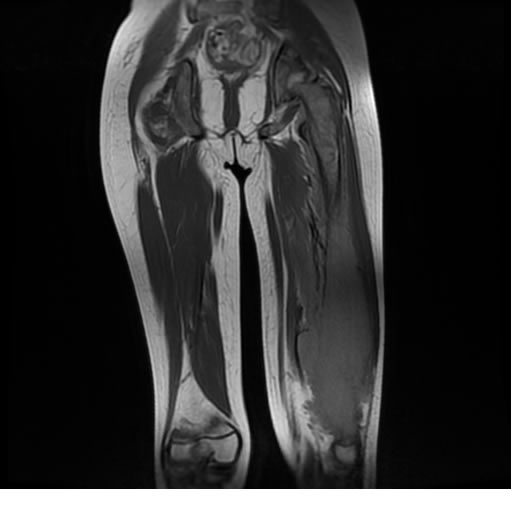

Se realiza estudio de MRI de muslo izquierdo en diferentes planos, con secuencias de Spin Echo, GRE; ponderadas a T1 y a T2, se utilizan pulsos de saturación de grasa y se administra medio de contraste IV a base de Gadolinio en base al peso del paciente.

La diáfisis femoral izquierda muestra reacción perióstica importante, se extiende desde el cuello del fémur, invade trocánteres, diáfisis femoral, medial y distal, es compatible con un proceso infeccioso óseo, el complejo muscular del muslo se ve edematizado.

Hallazgos en Resonancia Magnética (RM)

La resonancia es la modalidad de elección para valorar la extensión intramedular y la infiltración en tejidos blandos, brindando una imagen más detallada del compromiso tumoral. Los hallazgos característicos incluyen:

Lesión de señal heterogénea en secuencias T1 (hipointensa) y T2/STIR (hiperintensa), que refleja necrosis, hemorragia y contenido celular diverso.

Realce intenso y heterogéneo tras la administración de contraste (gadolino), lo que indica vascularización tumoral.

Compromiso de la médula ósea adyacente y de estructuras vecinas, como músculos y neurovasculatura.

Posible presencia de edema óseo y necrosis central.